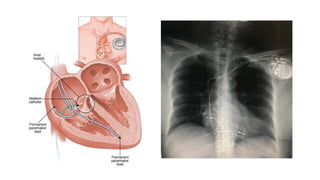

• Haz de His

• Sigue sobre el flanco derecho del

tabique del corazón, la inserción de

la valva septal de la válvula

tricúspide; llega a la porción

membranosa del tabique

interventricular

• Rama derecha: sigue el trayecto de

la trabécula septomarginal.

• Rama izquierda: atraviesa el tabique

interventricular, se ramifica en un

fascículo anterior y uno posterior

• Fibras de Purkinje

• Fibras en las paredes de los

ventrículos

Generación del impulso eléctrico en

nódulo sinusal.

Propagación de estímulos a través de

tractos internodales por aurícula derecha

e izquierda. (contracción de aurículas)

Estímulos llegan a nódulo AV, siguen su

recorrido a través del Haz de His.

Se propagan por ramas del haz de his y

finalmente pasan a la red de Purkinje.

(contracción de ventrículos)